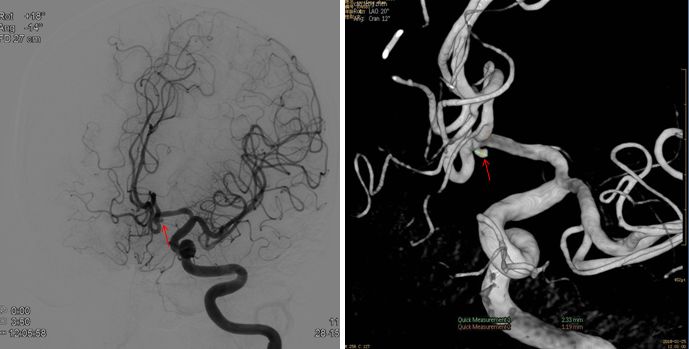

第一次1月25日 DSA—未行栓塞

第二次1月31日 DSA—未行栓塞(变化不大)